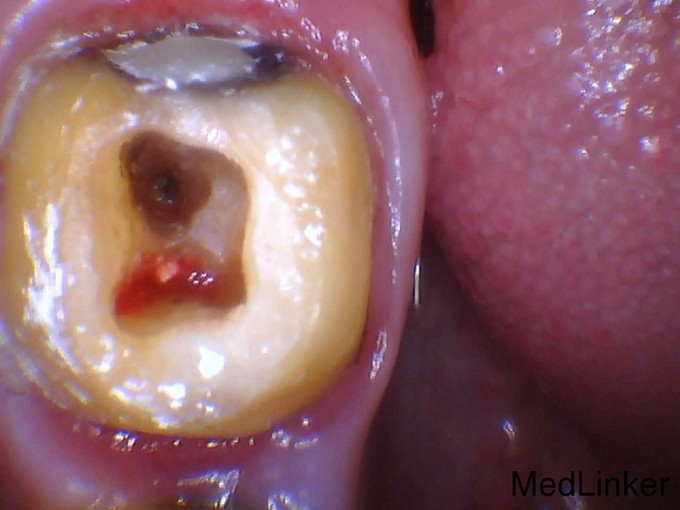

磨牙穿底的保守治疗

右下后牙两个月前外院治疗,一直疼痛不适,现要求重新治疗

磨牙穿底分根术治疗